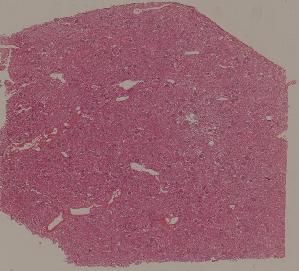

72.狼疮性肾炎